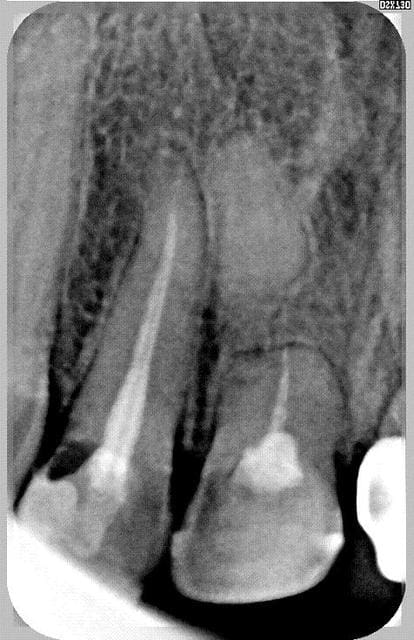

j'ai retrouvé un cas (radio)

44% dans cette étude, c'est une constation de résultat, ça ne peut être une prévision (prédictibilité?), je ne vois pas comment on pourait prévoir la réponse. Tout dépend de ce qui va compenser le trait de fracture, en cas de septicité ce sera obligatoirement un tissus de granulation (une endo même bonne ou un élément transfixiant restent un risque de contamination), pour avoir un tissus osseux c'est quand même du poker

et puis, il faudrait deux coups de chances là...

mais si on devait suivre une autre conduite je crois que la procédure serait différente et viserait à n'obturer a terme que le fragment coronaire (dans le cas ou l'evolution du trait est défavorable) et, éventuellement retirer par voie retro le fragment apical

cet autre cas ne m'appartient pas, pire je ne me souviens plus d'ou il vient ni a qui il est, j'espere que l'auteur sera clément et ne m'en voudra pas de le présenter car il illustre bien, par rapport au premier la cat si la réponse tissulaire est défavorable.